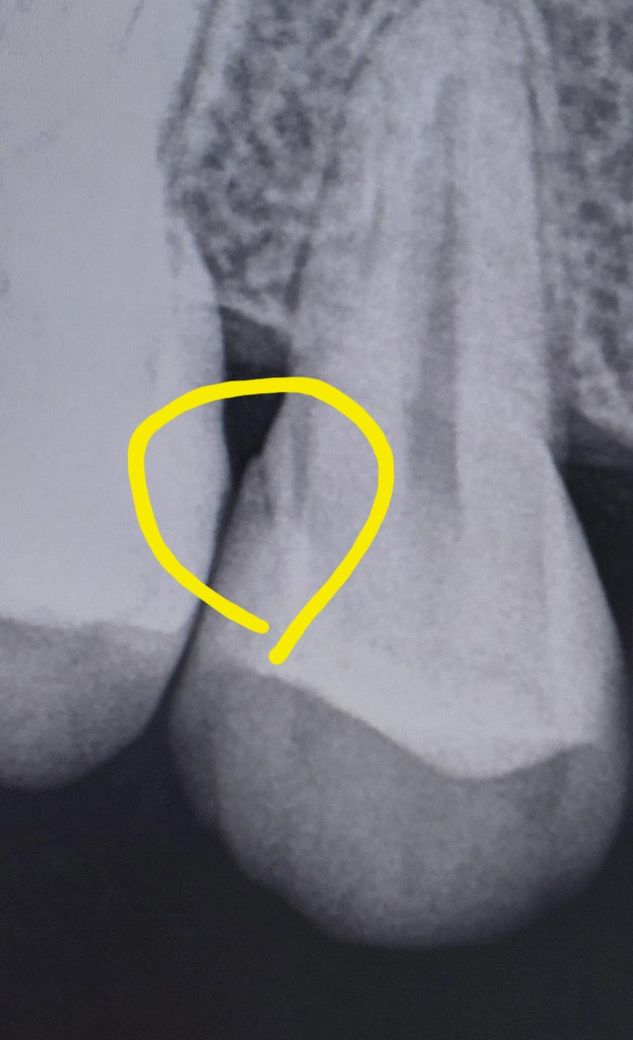

이거 치아 크랙인건가요?? 치과에서 엑스레이에 큐레이 검사에 직접 보셨는데 저거 크랙 아니라고하는데 금간거 아니죠?? 전 저부분에 통증이 있는거 같아서요

일단, 옆면에 치아 크랙이나 파절이 있는 경우라면 큐레이로 관찰할 수 있는게 아닙니다. 엑스레이상 조금 애매하긴 한데 여러 각도로 찍어봐야 더 정확히 알 수 있겠습니다